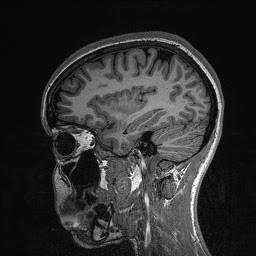

The images are taken in slices beginning from the outside and working its way in—that’s why my brain structures look smaller or bigger in some areas, and why my nose doesn’t show up until the end. And now, without further ado…my brain!

Eventually, when the lab technicians overlaid these images, they were able to create a 3D image of my entire brain, which might have looked something like this: